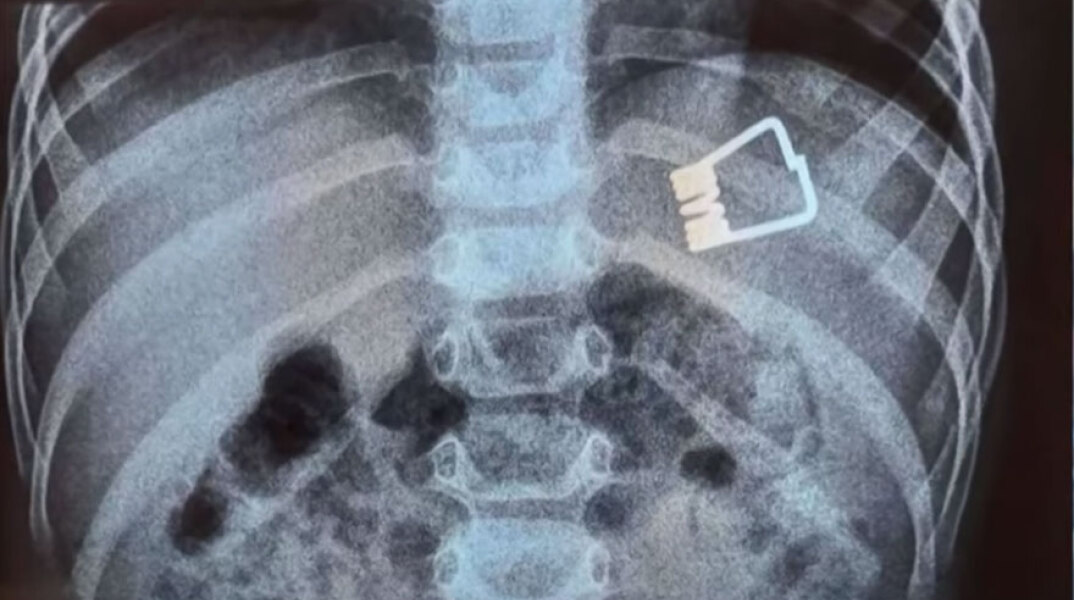

'Ενα μικρό παιδί μόλις 2 ετών από τη Λήμνο μεταφέρθηκε εσπευσμένα στο Ιπποκράτειο στη Θεσσαλονίκη επείδη κατάπιε μανταλάκι

Δύσκολες ώρες για ένα δίχρονο παιδάκι από τη Λήμνο, το οποίο κατάπιε ένα μανταλάκι. Μεταφέρθηκε εσπευσμένα στο Ιπποκράτειο Νοσοκομείο στη Θεσσαλονίκη. Εκεί, οι γιατροί κατάφεραν να βγάλουν το μανταλάκι από το στομάχι του με τη βοήθεια ενδοσκοπίου τελευταίας γενιάς.

Σύμφωνα με τα όσα μετέδωσε η ΕΡΤ, το παιδί κατάπιε το αντικείμενο στο σπίτι του και αμέσως σήμανε συναγερμός.

«Όταν το παιδί έφτασε εδώ αμέσως κινητοποιηθήκαμε, ενημερώσαμε τους αναισθησιολόγους, είχαμε έτοιμο το χειρουργικό κρεβάτι. Το παιδί έπρεπε να είναι νηστικό 6 με 8 ώρες και προβήκαμε στην αφαίρεση ενδοσκοπικά του ξένου σώματος» δήλωσε ο Ιωάννης Ξηνίας, αναπληρωτής καθηγητής Παιδιατρικής Γαστρεντερολογίας.